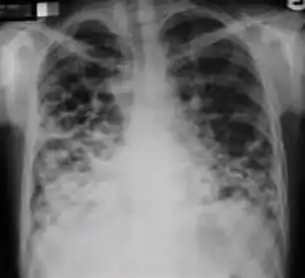

Chest x-ray showing coarse reticulonodular densities on the lower right lung of post-primary pulmonary TB.

Chest x-ray of Ghon's complex of active tuberculosis